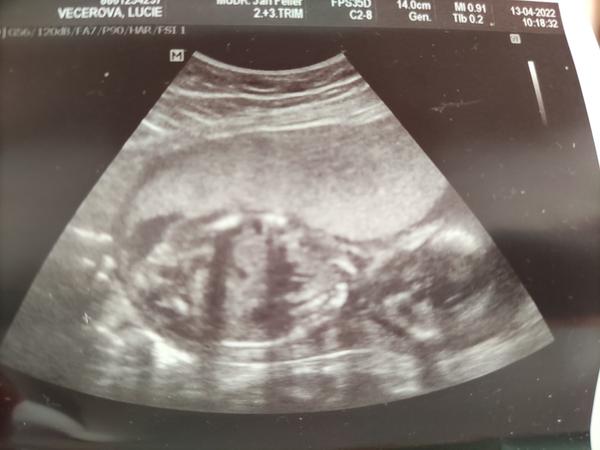

@lilian2111 teď jsem 17tt , nepadlo vůbec nic, nebyl asi ve své kůži, ani mi mimco nezmeril. Mám ještě fotku celého mimča a tohle mi udělal vedle, ať prý můžu doma lustit a zkoumat 😅

@lucynka721 Nedavala jsi ještě tady někde druhou fotku? Tam byl myslím trochu vidět hrbolek a to jsem si říkala že vypadá opravdu na chlapečka 🙂

@lilian2111 Dávala jsem k sobě na profil, ale jen otočenou. Pošlu

@lucynka721 Jj to je ona 🙂 no já bych řekla že je to kluk, my čekáme další holku a to bylo vždy na utz úplně jinak videt😀

@lilian2111 je to 19 TT, tam hrbolek už vidět myslím není.